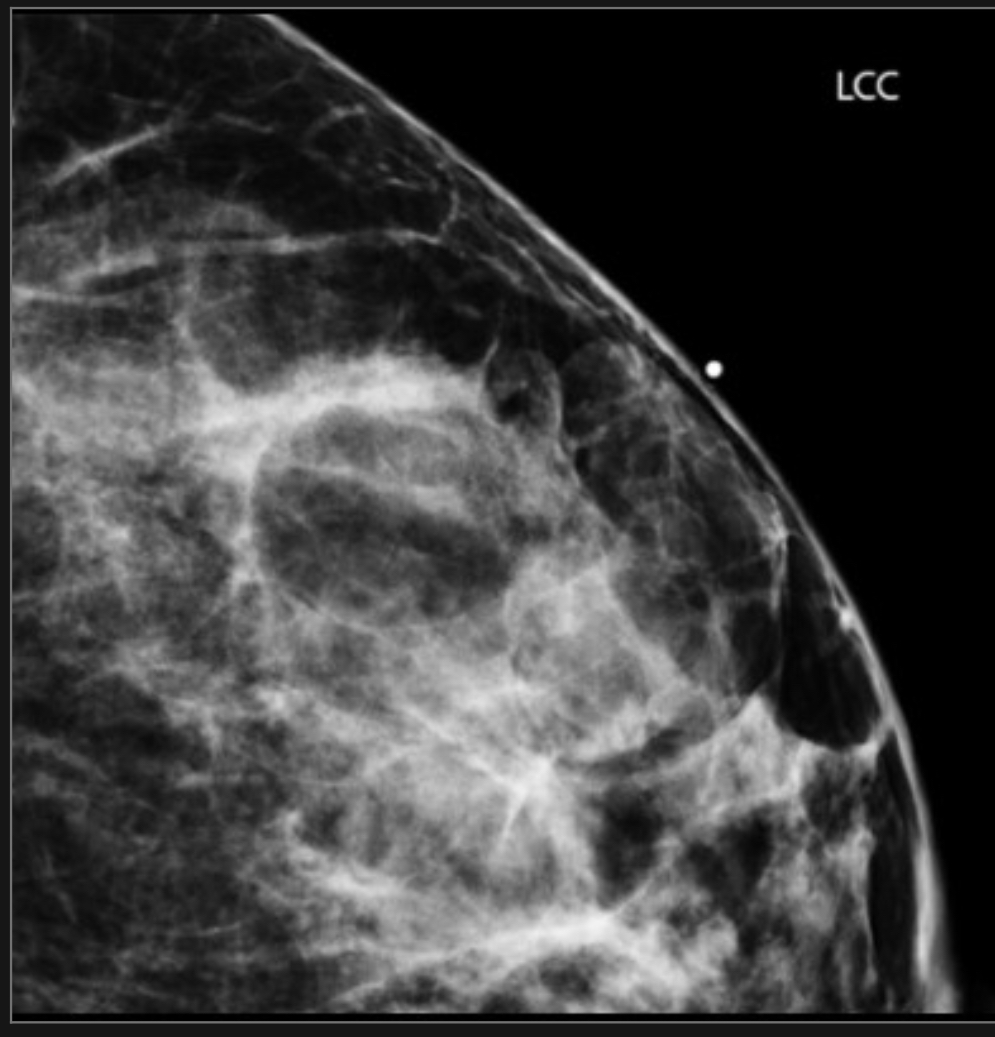

Normal fibroglandular tissue, island

feathery appearance with intervening lucent areas of this finding suggests that this is an island of glandular tissue rather than a mass, and its stability would support a BI-RADS 2 (benign) or BI-RADS 1 (negative) assessment

**here called a focal asymmetry bc normal CC view doesn’t image this portion of the breast-need an extended CC view